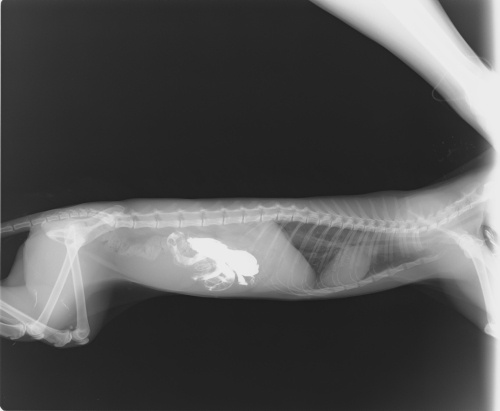

Dün ve bu gün onu başka bir doktor yanına götürdüm, röntgen çekdiker dün ve bu gün yine aynı şekilde röntken ve ultrason çekildi kedinin karnına. (Röntgen resmini aşağıya atıyorum)

Doktor bana röntgende yabancı bir cisim gözüktüğünü ve yarın ameliyat için oraya götürmemi istedi, yarın yeniden röntgen çekip ameliyat yapmak istiyor.

Ben röntgeni her daim kediyi götürdüğüm doktora gösterdiğimde bana açık bağırsak ameliyatının riskli olduğunu kediye zarar dahi verilebilir bu ameliyatla diye söyledi. Bu doktor daha çok FİP ten şüphelendiğini söyledi bana, kedinin mide borusununda fazla normalden fazla genişlendiğinjde söyledi. Bu gün kediye iğne yaptı ve yarın yeniden gelmemi söyledi. Eve döndükten sonra kedi röntgen çektirdiğimiz klinikte tabaşir yutmuştu onu kustu daha sonra ona yemek verdim suyla karıştırarak onu kusmadı.

Tıkanıklık neredeymiş söylediler mi? Sanırım mideyi biraz geçmiş bağırsakta ilerlemiyor o sıvı.

Mide kasıldığında, çıkışa gidemiyor ve yediğini ters olarak ağızdan çıkartıyor.

Ancak kedinize baryum içirmişler sanırm. Beyaz görünen madde o. O temizlenmeden alabiliyorlar mıymış ameliyata?

Teşekkür ederim, tüy değilde ince ipe ben,er bir şey olduğunu söyledi resimde o beyaz görünen gölgenin alt kısmında aslında gözüküyor.